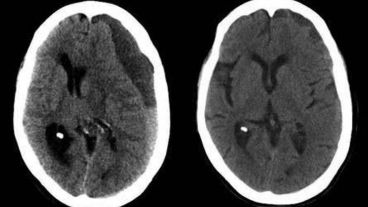

El ministro de Salud de la Nación, Ginés González García, continuaba internado este miércoles a la noche en el Sanatorio Otamendi de la ciudad de Buenos Aires por un hematoma subdural y aseguró que este jueves a la mañana recibirá el alta y volverá a trabajar. "Estoy fenómeno", aseguró en diálogo con Telenoche.

En 2013, la expresidenta Cristina Fernández de Kirchner, fue operada en la Fundación Favoloro, luego de que se le detectara la misma afección, un hematoma subdural, tras presentar un cuadro de cefaleas.

El propio ministro confirmó que tiene la misa afección por la que fue operada Cristina e incluso bromeó: "No es por disciplina partidaria".